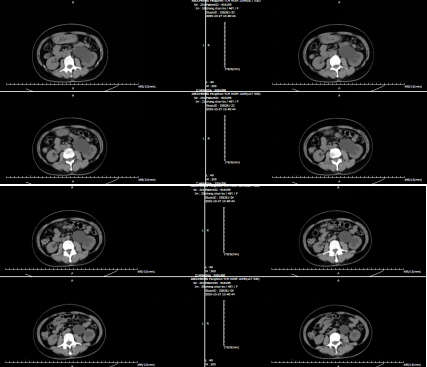

患者收住我院泌尿外科,崔克主任带领科室团队与熊六林主任医师进行病历探讨后制定腹腔镜肾盂输尿管成形术的手术方式,并稳步推进各项诊疗工作:1. 明确狭窄,专家协作定方案:术前通过泌尿系B 超、CT 等检查,明确 “窄在哪、窄多长、肾积水多严重”等问题。因张女士肾积水程度重且狭窄位置深,熊六林主任医师精准评估,排除手术禁忌后,确定采用 “腹腔镜下肾盂输尿管成形术”,并备好血管保护、支架管植入等预案。2. 精准吻合,“严丝合缝”规避风险:术中探查发现狭窄原因为异位血管束压迫所致,肾周粘连较重,熊六林主任根据情况,实时调整操作,精准切除 2 厘米狭窄段,吻合肾盂与输尿管后成功置入支架管。手术历时 2 小时 46分钟,出血仅 20 毫升,全程未出现血管损伤、邻近脏器牵涉等并发症。3. 细致护理,中西调护 “新接口”:术后监测尿量、预防感染,配合穴位贴敷、手指点穴等中医特色护理,患者恢复良好,未出现吻合口漏尿、感染等并发症。患者术后第 6天复查泌尿系CT提示肾积水明显减轻,肾功能正常,腰胀症状明显缓解;第 7 天出院;预期术后1 个月返院拔除支架管。张女士反馈:“微创恢复快,专家协作让人放心。”

复查CT见下图: